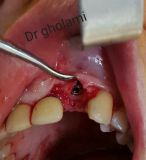

معرفی سیستم SPI همراه با جراحی زنده و Immediate Loading - آبان ۹۵

جراح وسخنران : استاد دکتر غلامعلی غلامی